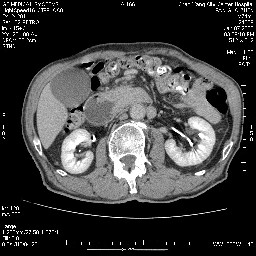

女,74岁,呕吐10余日

壶腹部的占位性病变,考虑为十二指肠癌并梗阻,但脾内多发性低密度区为转移吗?

还有胃、脾之间可见有侧支循环建立。左肾盂积水。

十二指肠水平段腔内占位伴梗阻,中等度较为均匀的强化,洗脱慢,区域淋巴结显示增多,符合腺癌表现。下腔静脉变异。

十二指肠降段扩张,水平段狭窄成鼠尾状,肠壁明显增厚,胰腺勾突增大成不均匀强化,其内可见低密度区,胆囊增大,1十二指肠水平段腺癌侵犯胰腺勾突可能大,2胰腺癌侵犯十二指肠(只有胆囊增大没有肝内外胆管扩张不好解释)代除外.

十二指肠降段扩张,水平段狭窄成鼠尾状,肠壁明显增厚,胰腺勾突增大成不均匀强化,其内可见低密度区,胆囊增大,1十二指肠水平段腺癌侵犯胰腺勾突可能大,2胰腺癌侵犯十二指肠 。

今日手术结果:胰腺钩突癌侵犯十二直肠,腹腔淋巴结转移.